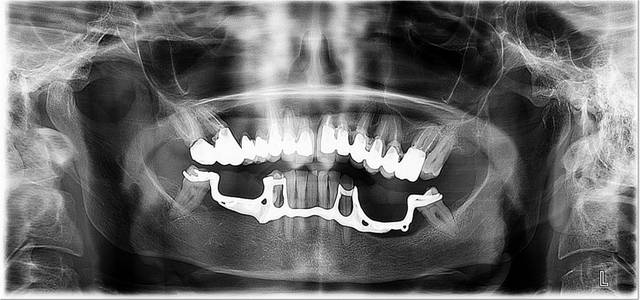

Un exemple de réhabilitation globale implanto-portée :

Patient 55ans, fumeur

Doléance, maxillaire supérieur

Projet prothétique, mise en charge immédiate avec pose d’un bridge à armature métal sur pilier cone morse

Chirurgie, extraction, implantation, mise en charge immédiate

Projet implantaire 8 implants, prothèse fixe

Protocole de MCI POSITDENTAL

Le bridge est posé en fin de chirurgie sur les piliers prévus pour la prothèse d’usage. Il est maintenu en place par friction ce qui évite l’utilisation de ciment de scellement. Son insertion se fait par emboitement comme il est présenté sur la vidéo. Son retrait se fait par percutions avec un arrache couronne.

Pièces jointes :

OTP pré-opératoire

Otp pr  op wx6ukb - Eugenol